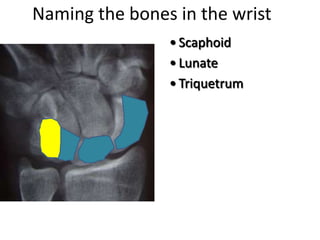

- Naming the bones, joints, tendons, nerves and skin landmarks of the hand and wrist.